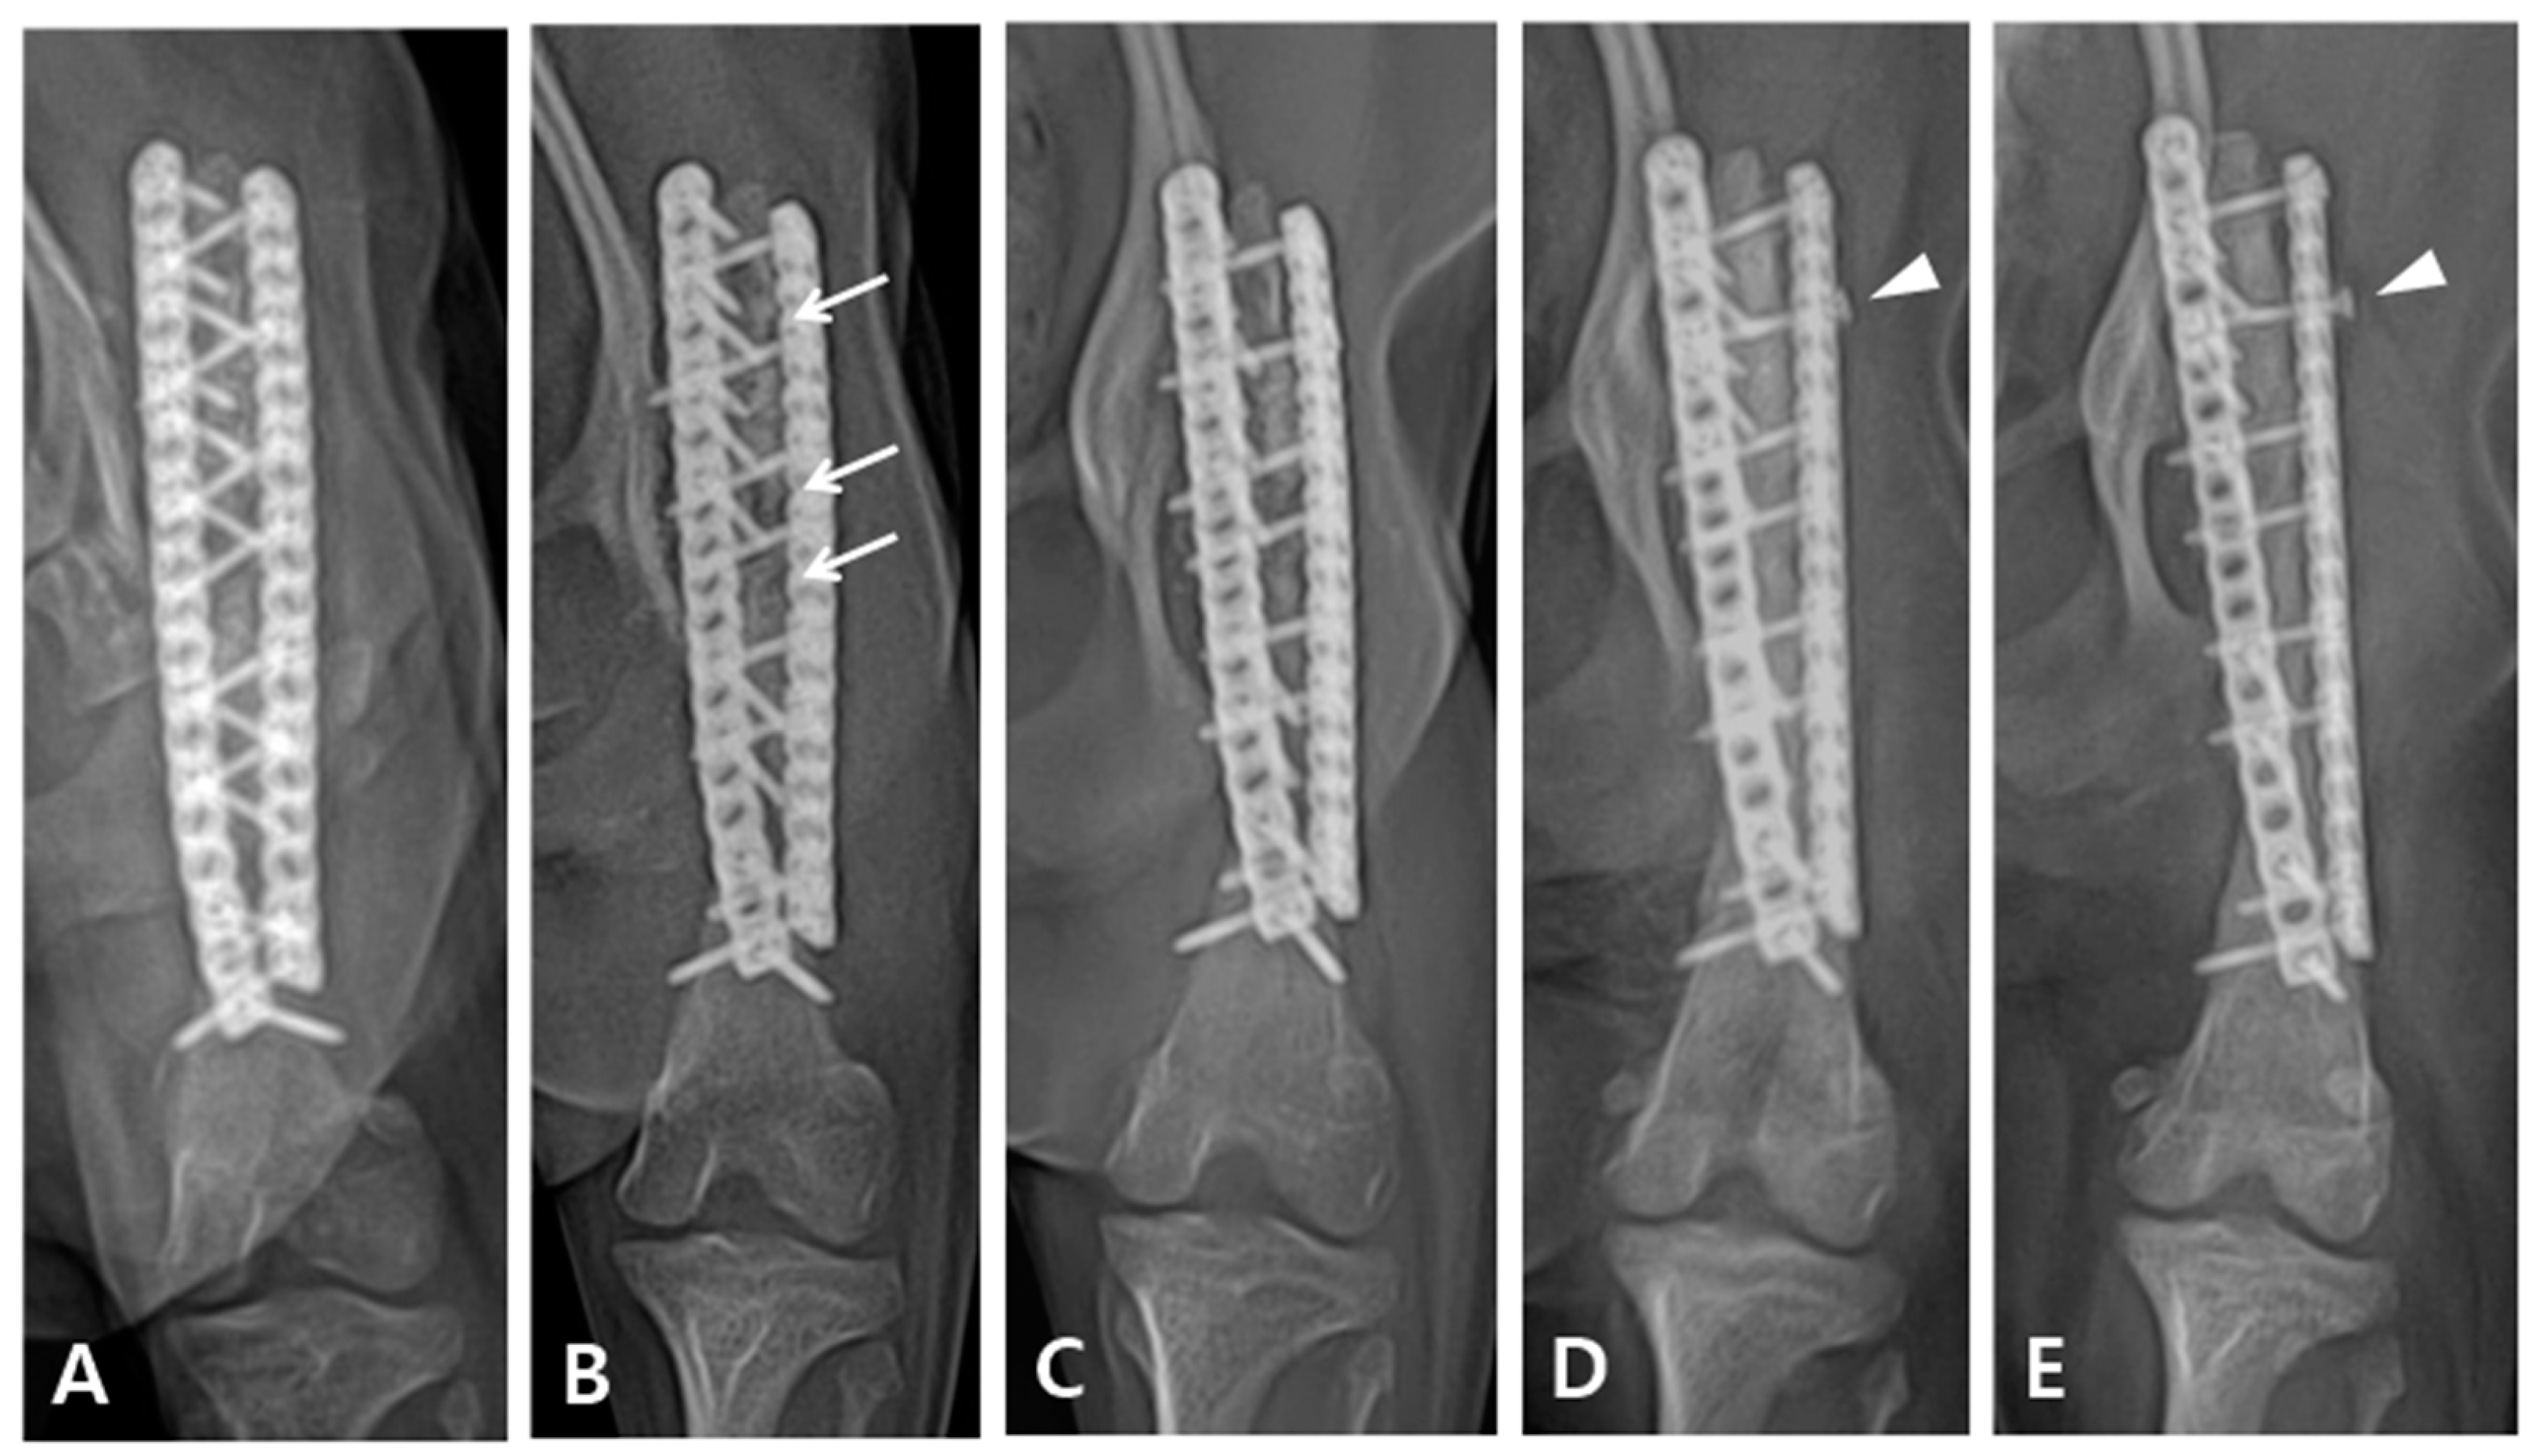

Figure 4. Follow-up radiography after the operation. (A) Two weeks after the operation. (B) Four weeks after the operation. Some bone resorption observed in the grafted area (arrow). (C) Three months after the operation. The parts that were radiolucent at the last follow-up appeared more opaque. (D) Eighteen months after the operation. The cortex exhibited continuity and there was no visible fracture line, indicating that the bones had completely fused. However, it was confirmed that a screw in the lateral plate had loosened (arrow head). (E) Four years after the operation. The results from the last follow up were maintained.

Immediately after surgery, the patient exhibited knuckling and was unable to bear weight. However, a neurological examination revealed no nerve damage. Limb shortening compared with the contralateral side was observed after the operation. Although the patient could partially bear weight, knuckling still persisted for six weeks after the operation. Three months post-operatively, the patient was able to fully bear weight in the limb extended position, with complete resolution of knuckling. On radiographic follow-up, the grafted bone showed temporarily increased lucency four weeks postoperatively, which recovered in three months after the operation (Figure 4B,C). Eighteen months postoperatively, radiographic examination revealed complete bone healing; however, loosening of the proximal second screw in the lateral plate was observed (Figure 4D). The patient was followed up for four years after the operation and exhibited satisfactory gait during walking and trotting; however, some lameness was noted following intense exercise or galloping.

In the early stages of direct bone healing, also known as primary bone healing, radiographic fracture lines remain visible. During contact healing, there was no resorption of the fragment tip, and the cutting cone progressed across the fracture gap and became radiographically opaque. In clinical cases of simple transverse fractures treated with rigid fixation with compression, the fracture line may slowly disappear without forming callus [16,17]. In our case, as shown in Figure 3B, partial absorption of the grafted bone was observed 4 weeks after surgery, and the osteotomy line between the grafted coccygeal bone and the distal bone fragment was visible radiographically. However, in Figure 3C, taken 3 months later, the previously seen lucency became opaque, and in Figure 3D, taken after 8 months, the osteotomy line completely disappeared. Despite the extended time required for complete bone healing, rigid fixation was maintained for an extended period using locking plates and screws, which facilitated healing without callus formation.